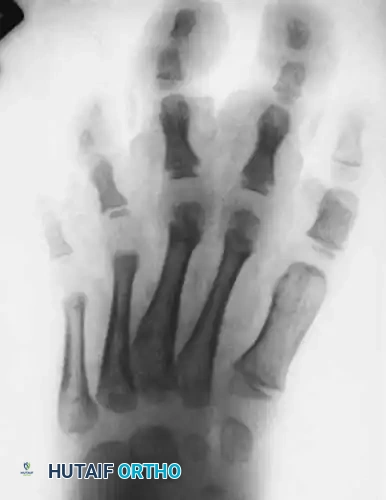

Fig. 26-5 B, Anteroposterior radiograph; note soft-tissue hypertrophy of second and third ray phalanges.